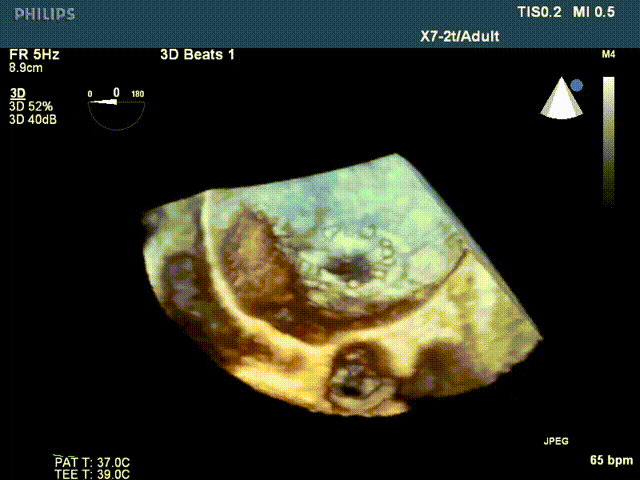

术后超声: